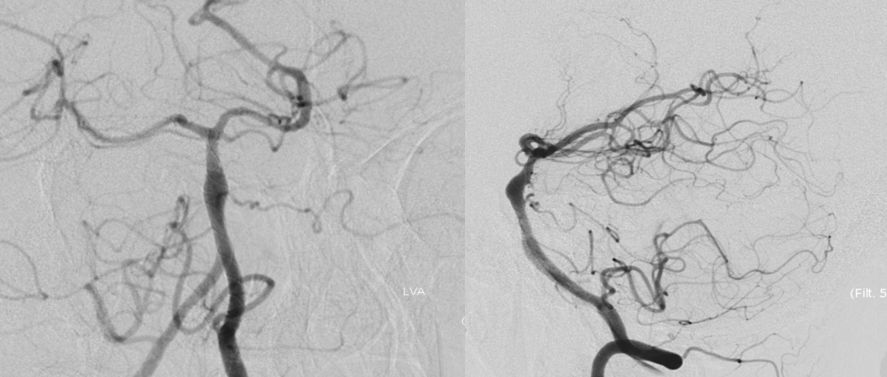

本院DSA:基底动脉巨大夹层动脉瘤,双侧后交通动脉未见明显开放(图6)。

图6

4、支架完全释放后造影可见支架完全覆盖动脉瘤,贴壁良好,载瘤动脉及支架覆盖的双侧AICA及右侧椎动脉通畅(图11)。

图11